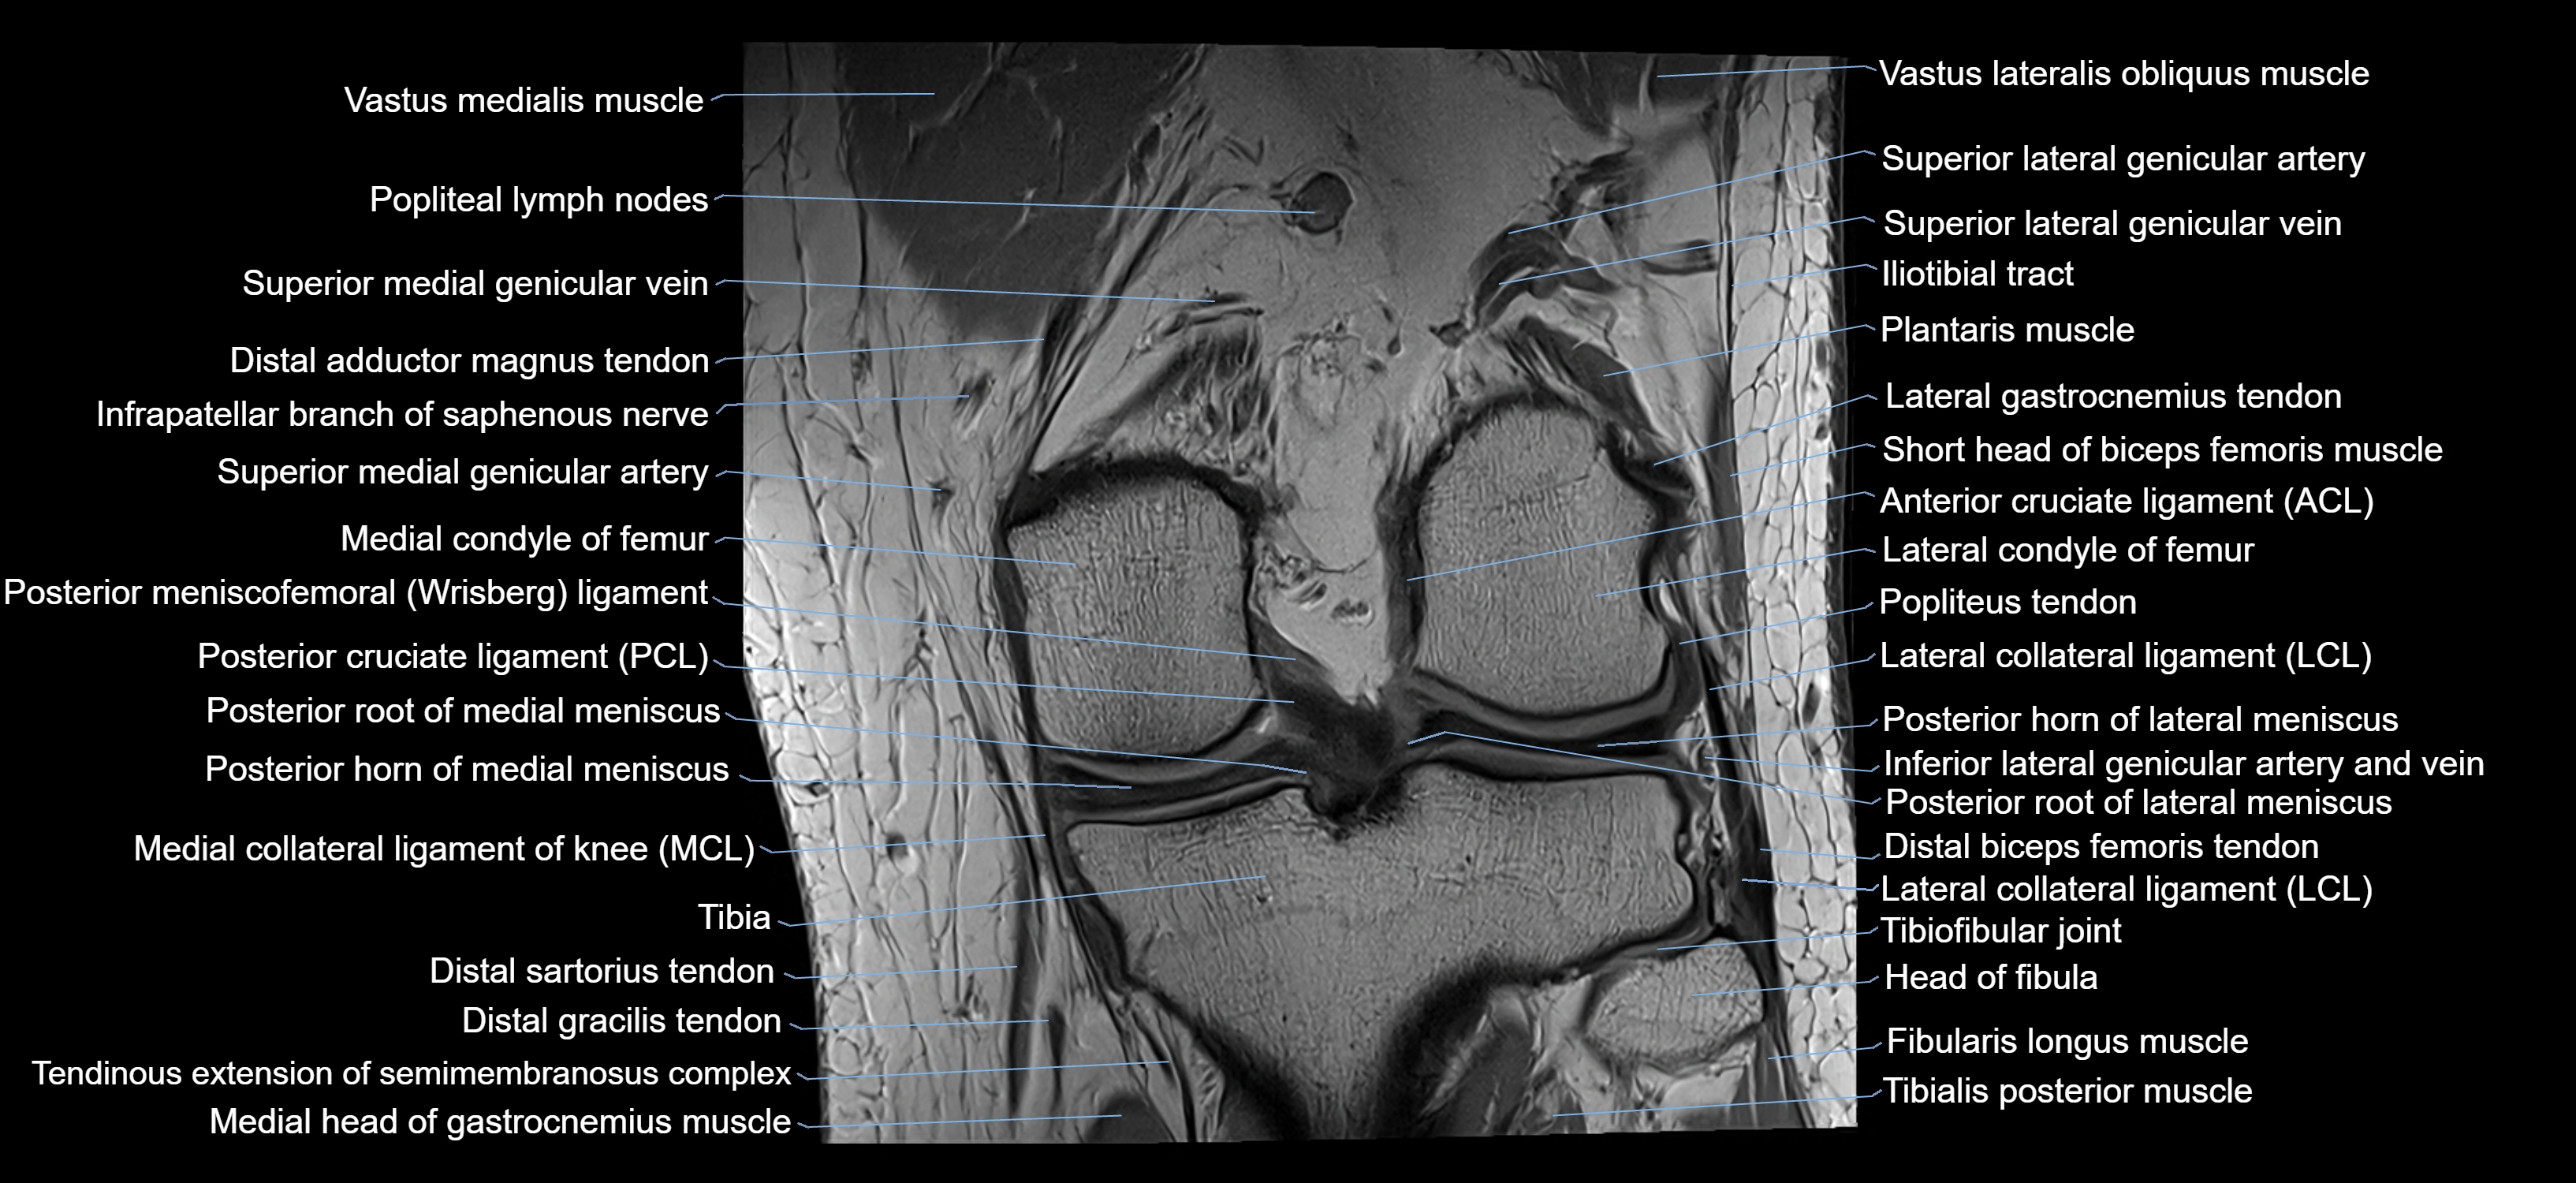

- Medial collateral ligament

- Medial condyle of femur

- Medial condyle of tibia

- Medial meniscus

- Medial patellar retinaculum

- Posterior cruciate ligament

- Posterior horn of lateral meniscus

- Posterior horn of medial meniscus

- Posterior root of lateral meniscus

- Posterior root of medial meniscus

- Superior lateral genicular artery

- Superior lateral genicular vein

- Superior medial genicular artery

- Superior medial genicular vein